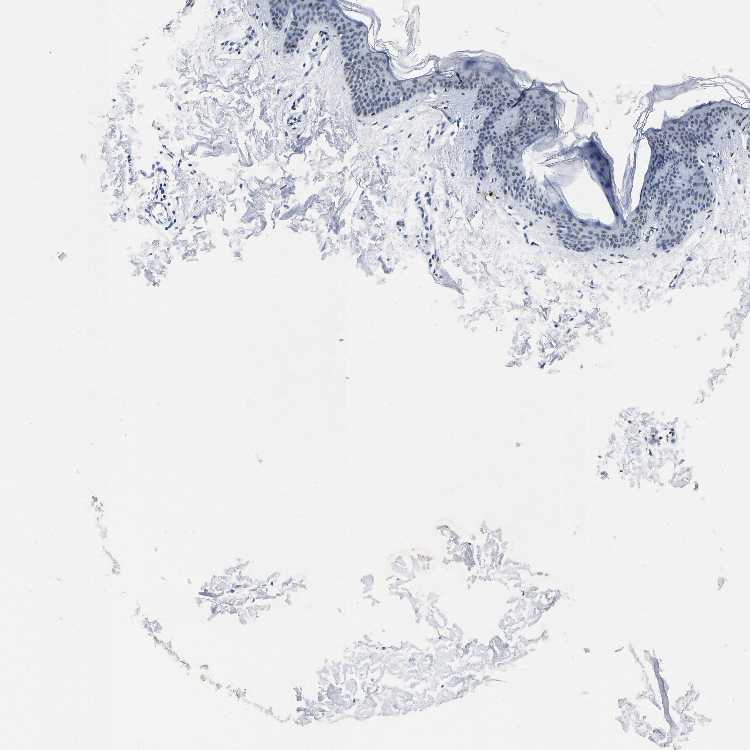

SKIN 1 - Antibody stainingi

Antibody staining in the annotated cell types in the current human tissue is reported as not detected, low, medium, or high, based on conventional immunohistochemistry profiling in selected tissues. This score is based on the combination of the staining intensity and fraction of stained cells.

Each image is clickable and will lead to virtual microscopy that enables deeper exploration of all samples and also displays staining intensity scores, fraction scores and subcellular localization as well as patient and tissue information for each sample.

Antibody HPA020448

Langerhans Low

Fibroblasts Not detected

Keratinocytes Not detected

Melanocytes Low